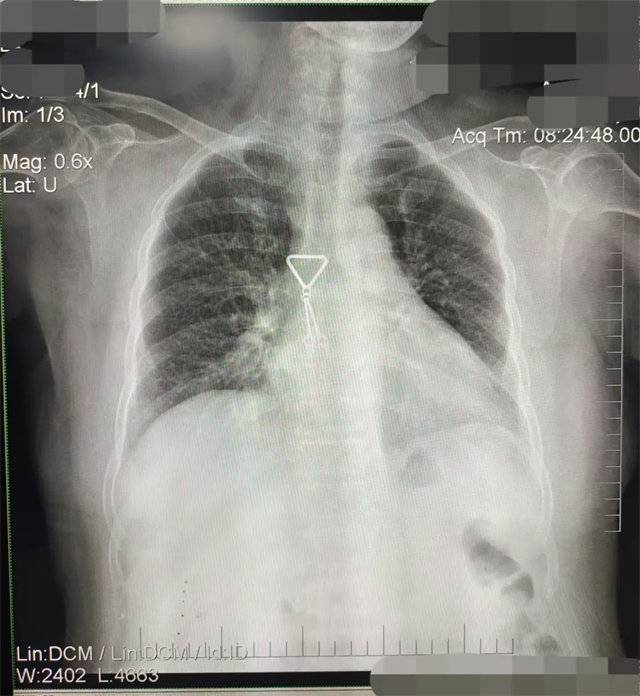

拍攝的不合格胸片的缺陷和解決方法

缺陷:兩肩胛骨未拉開肺野之外,吸氣不完全,且存在金屬飾品遮擋。

解決:去除金屬飾品及內(nèi)衣后重新按標準體位攝片即可。